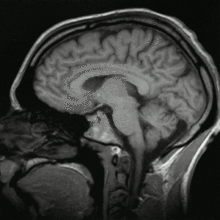

L'irm (imagerie par résonance magnétiques) est un examen qui permet d'étudier avec une grande précision de nombreux organes tels que le cerveau, la colonne vertébrale, les articulations et les tissus mous. Elle complète souvent une radigraphie car elle est beaucoup plus précise, permet de rendre visible des éléments qui ne pouvaient l'être avec une simple radio. Elle permet d'avoir des images en deux ou trois dimensions.

Elle utilise un champ magnétique et des ondes radio. Aucune radiation ionisante n'est émise.

On peut obtenir des images car l'Homme possède de nombreux atomes d'hydrogène.Placés dans un puissant champ magnétique, tous les atomes d'hydrogène s'orientent dans la même direction : ils sont alors excités par des ondes radio durant une très courte période . A l'arrêt de cette stimulation, les atomes restituent l'énergie accumulée en produisant un signal qui est enregistré et qui donne un image.